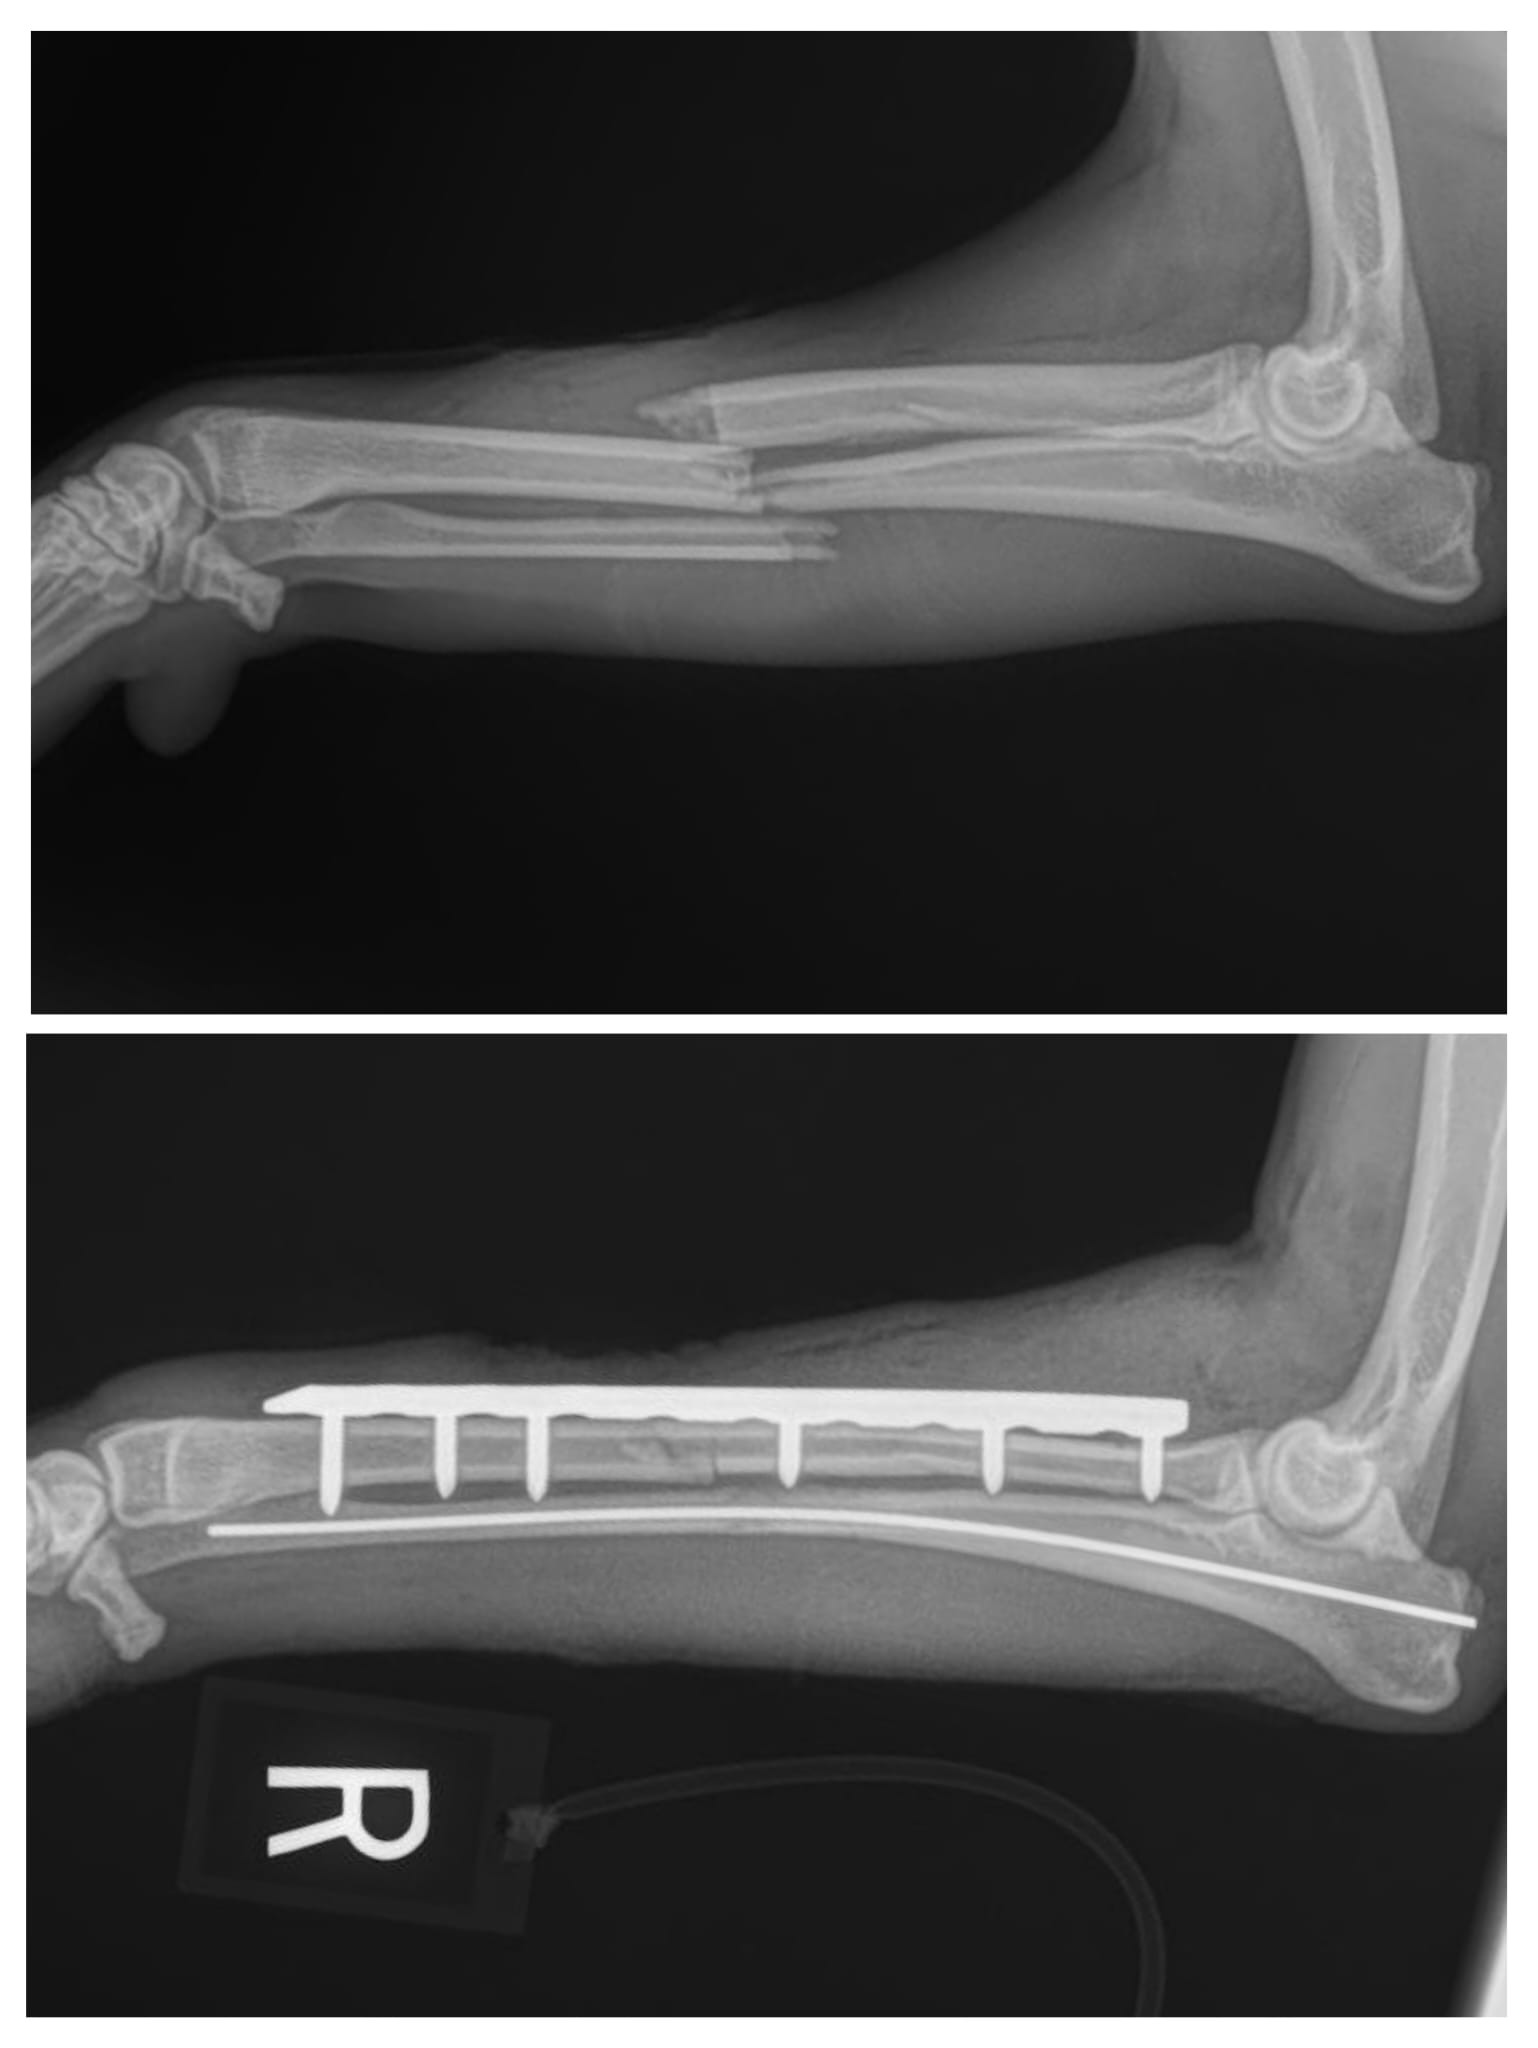

Our practice provides several advanced surgical procedures, including certain stifle (knee) and hip surgeries, internal fracture repair, laparoscopy, and total ear canal ablation with lateral bulla osteotomy, which are commonly referred to specialty centers. We want to be clear that our veterinarians are not board-certified surgeons, and we do not present ourselves as specialists.

At the same time, with thoughtful case selection and experience, we are able to perform many advanced procedures successfully and have helped many pets recover and thrive. Our goal is always to act in the best interest of each patient while ensuring owners are fully informed of all available options. Thank you for entrusting us with your pet’s care.